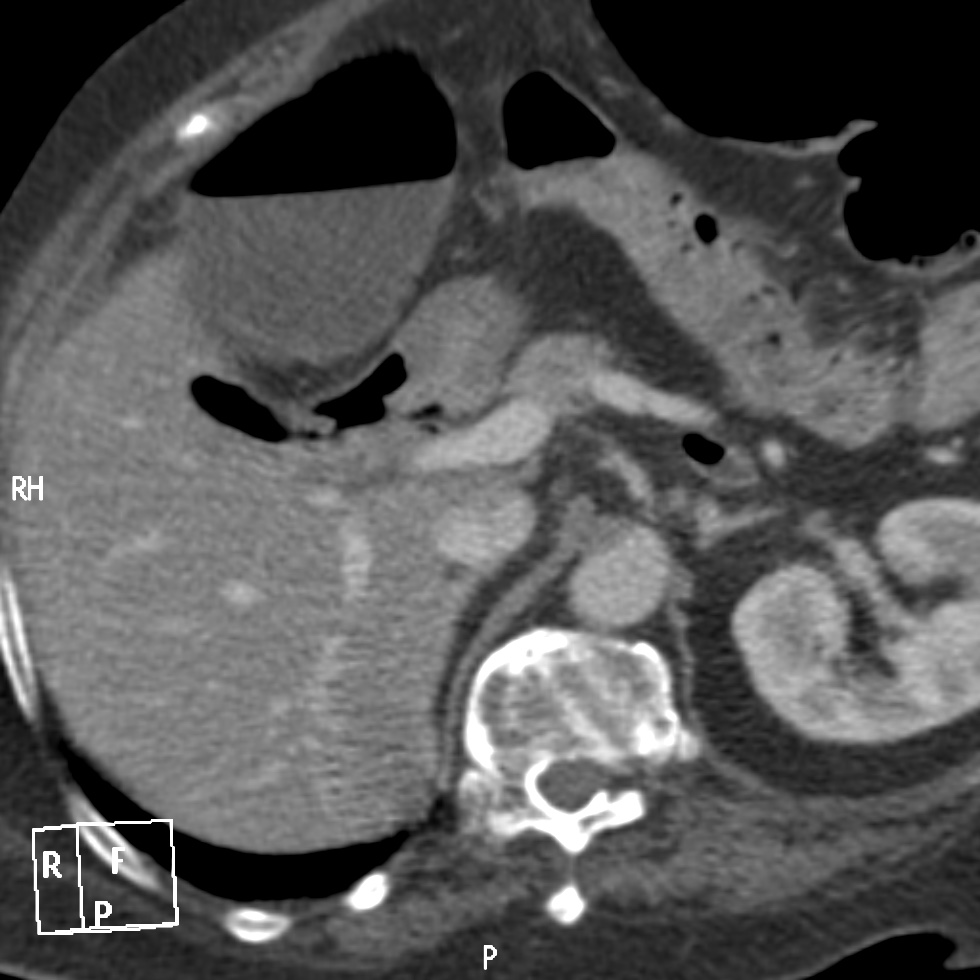

Se realiza un TC abdominal sin contraste:

Observar como posterior a la litiasis hay un cambio de calibre, el segmento que queda de ileon y el colon no están distendidos.

No encontramos ante un Ileo biliar, una obstucción intestinal mecánica ocasionada por una litaisis enclavada en el íleon terminal. La paciente estaba colecistectomizada, por tanto, lo más probable es que haya sido producido por una litiasis residual que pasó desapercibida.

- Dilatación por obstrucción de asas de delgado.

- Aerobilia.

- Litiasis (2 – 3 cm aprox). Hay que tener cuidado ya que muchas litiasis no están calcificadas y su densidad puede ser similar al contenido del intestino. Pueden ser multiples, por tanto hay que poner atención para que no pasen desapercibidas y evitar las recidivas.